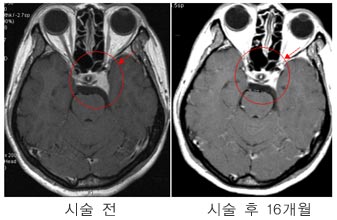

³ú¼ö¸·Á¾

ÅÍŰ¾È

»óºÎ ¼ö¸·Á¾ ȯÀÚÀÇ MRI »çÁø.°¨¸¶³ªÀÌÇÁ

¹æ»ç¼±¼ö¼ú 16°³¿ùÈÄ Á¾¾çÀÇ Å©±â°¡ ÇöÀúÈ÷

°¨¼ÒÇÏ¿´´Ù

³úÇϼöüÁ¾¾ç

¼ºÀåÈ£¸£¸ó

°ú´ÙºÐºñÇü °Å´ë³úÇϼöü Á¾¾çÀÇ °æ¿ì

°æÁ¢Çü°ñ ³úÇϼöü ÀûÃâ¼úÀ» ½ÃÇà ÈÄ ³²Àº

Á¾¾ç¿¡ ´ëÇØ °¨¸¶³ªÀÌÇÁ ¹æ»ç¼± ¼ö¼úÀ»

½ÃÇàÇÏ¿© ¿ÏÄ¡µÊ.¼ºÀåÈ£¸£¸ó ¼öÄ¡µµ ¼ö¼ú

Àü 58.6 ng/ml¿¡¼ °¨¸¶³ªÀÌÇÁ ½Ã¼ú ÈÄ

28°³¿ù° Á¤»ó¼öÄ¡ÀÎ 2.3 ng/mlÀ¸·Î °¨¼ÒµÇ¾ú´Ù.